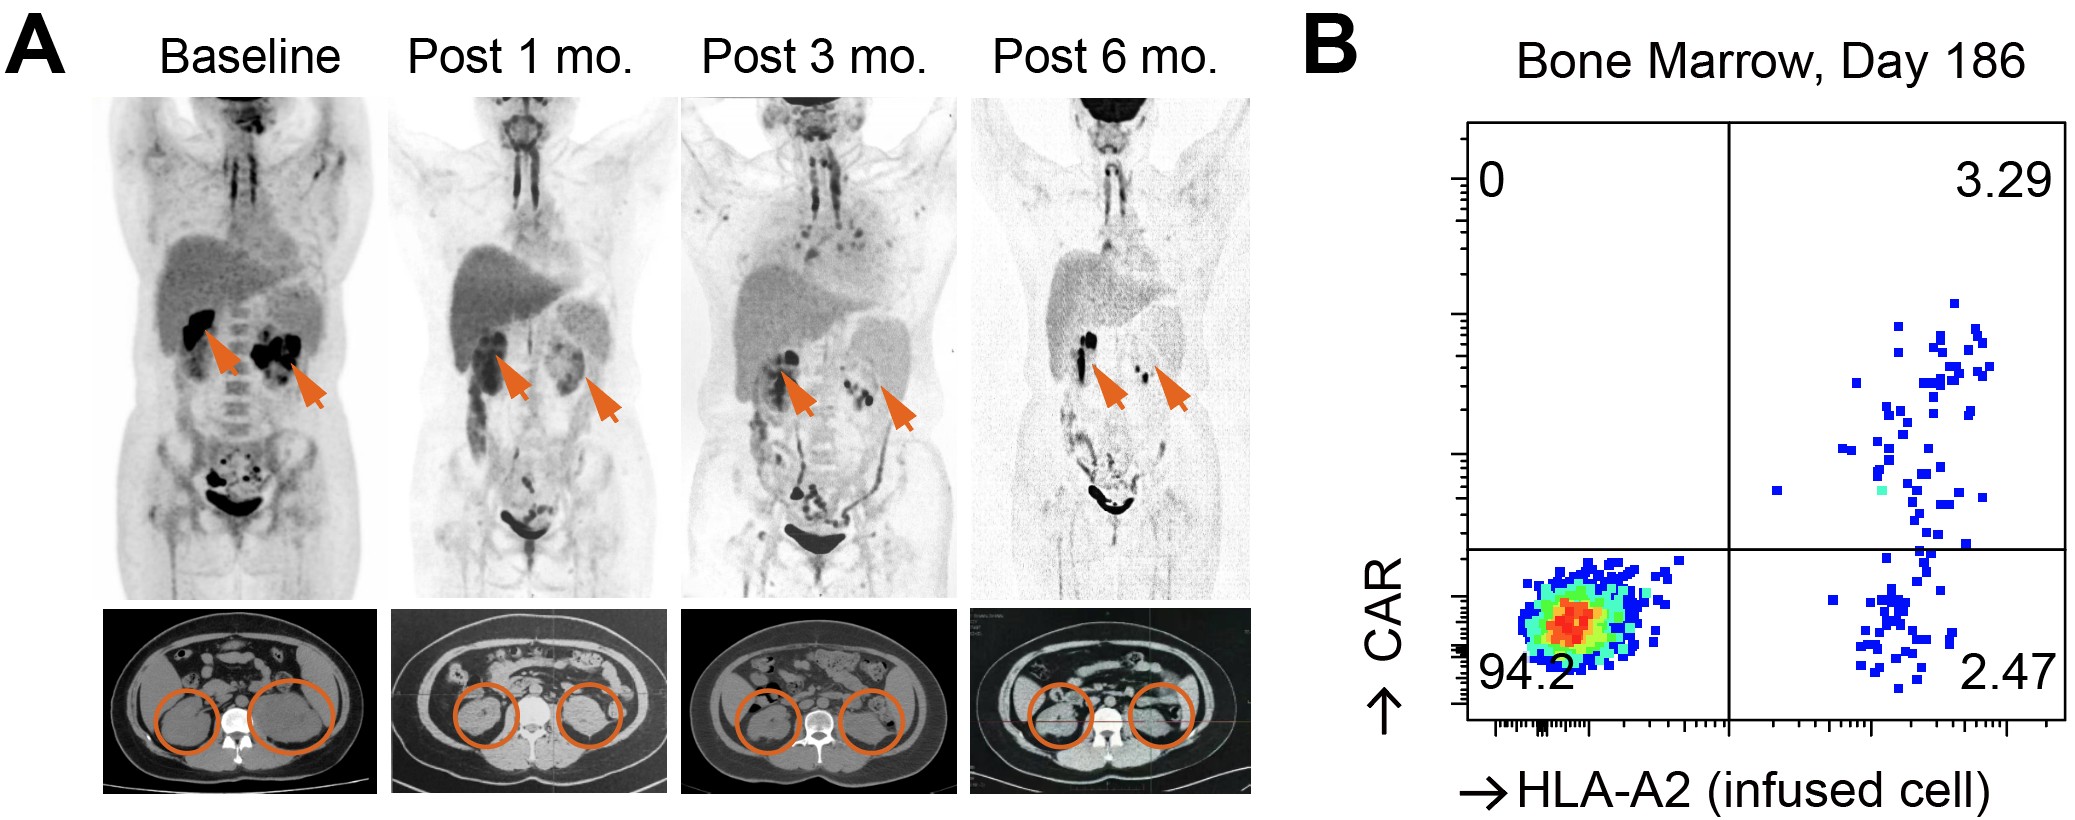

通过对输入产品中残存CD3+ CAR-T的扩增动力学分析,研究者推测SPPL3敲除所形成的“糖苷盾”能够避免GvHD,而保留TCR基底信号则可能对维持T细胞长期存活至关重要。基于这一假设,团队进一步开展了仅敲除SPPL3、保留TCR的第二项临床试验。结果显示,患者体内的CAR-T可持续存在6个月以上,未观察到典型GvHD或严重免疫并发症,部分患者获得持久缓解(图三)。

图三、SPPL3单敲策略的CAR-T的临床结果